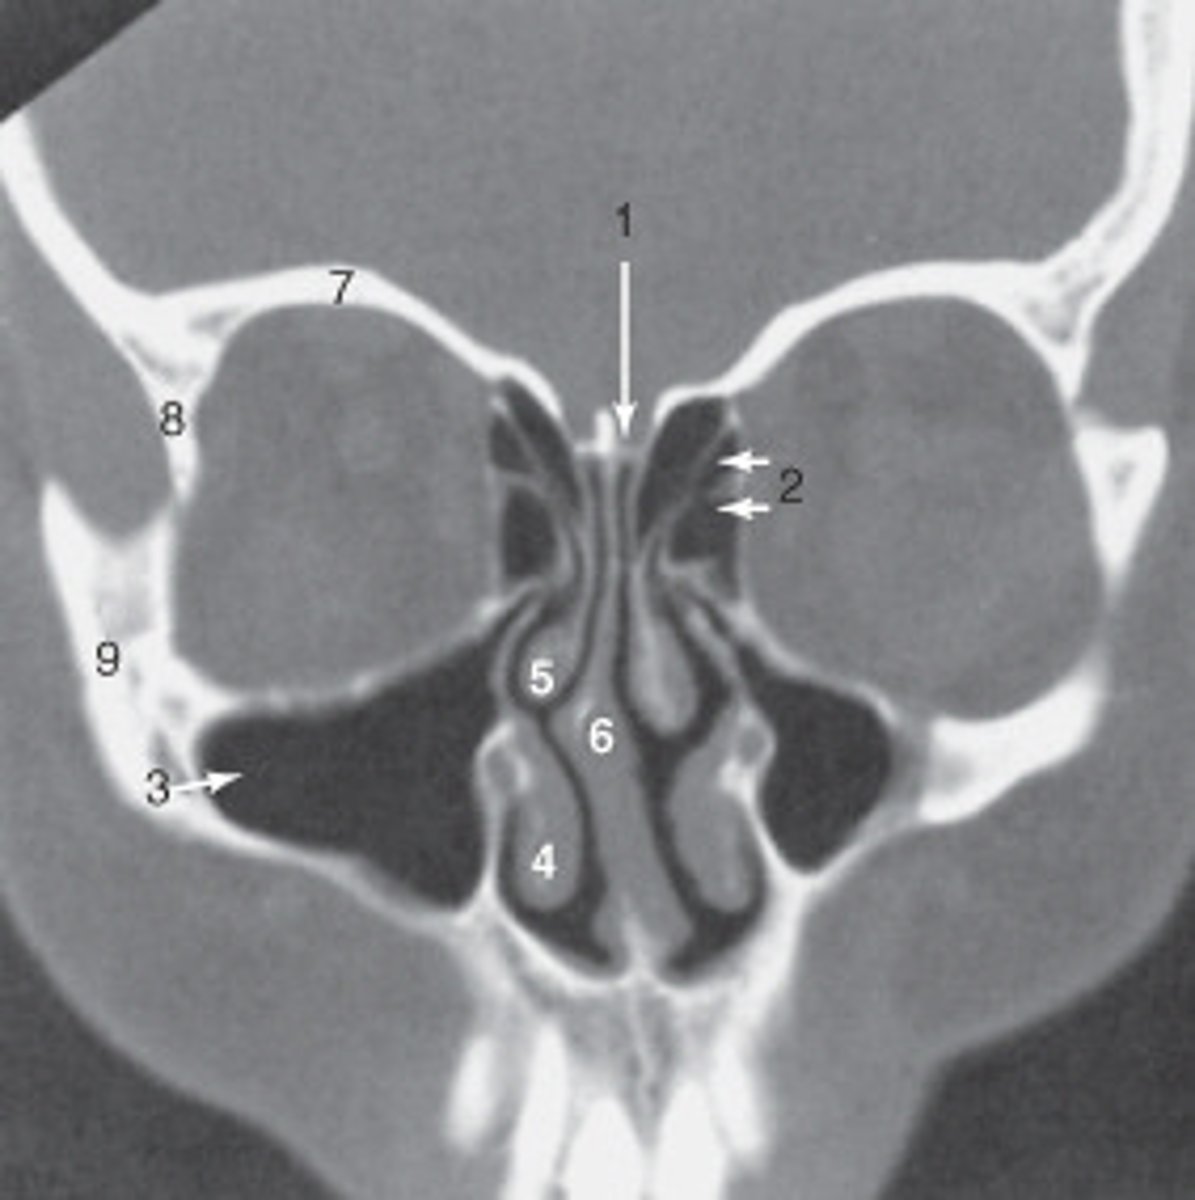

The internal jugular vein is labeled:

<p>The internal jugular vein is labeled:</p>

the parotid gland is labeled:

<p>the parotid gland is labeled:</p>

the structure labeled as 8 is the:

<p>the structure labeled as 8 is the:</p>